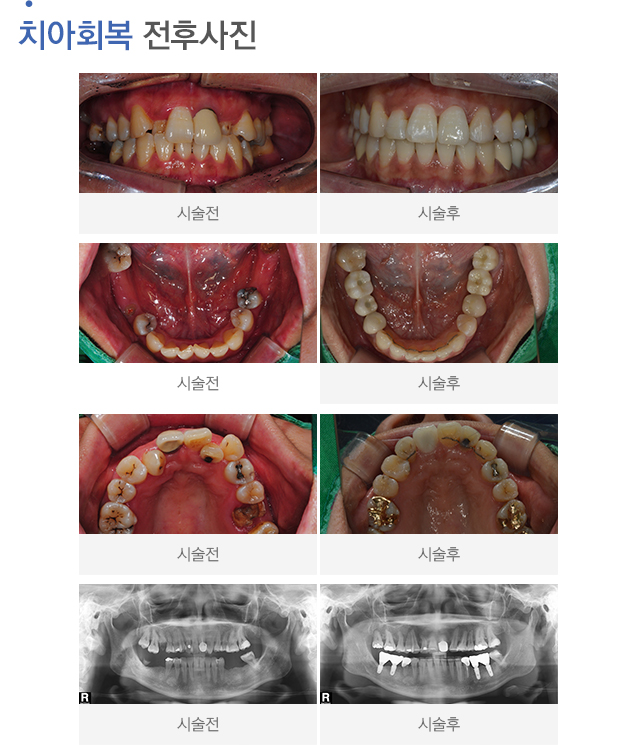

• 전후사진더보기